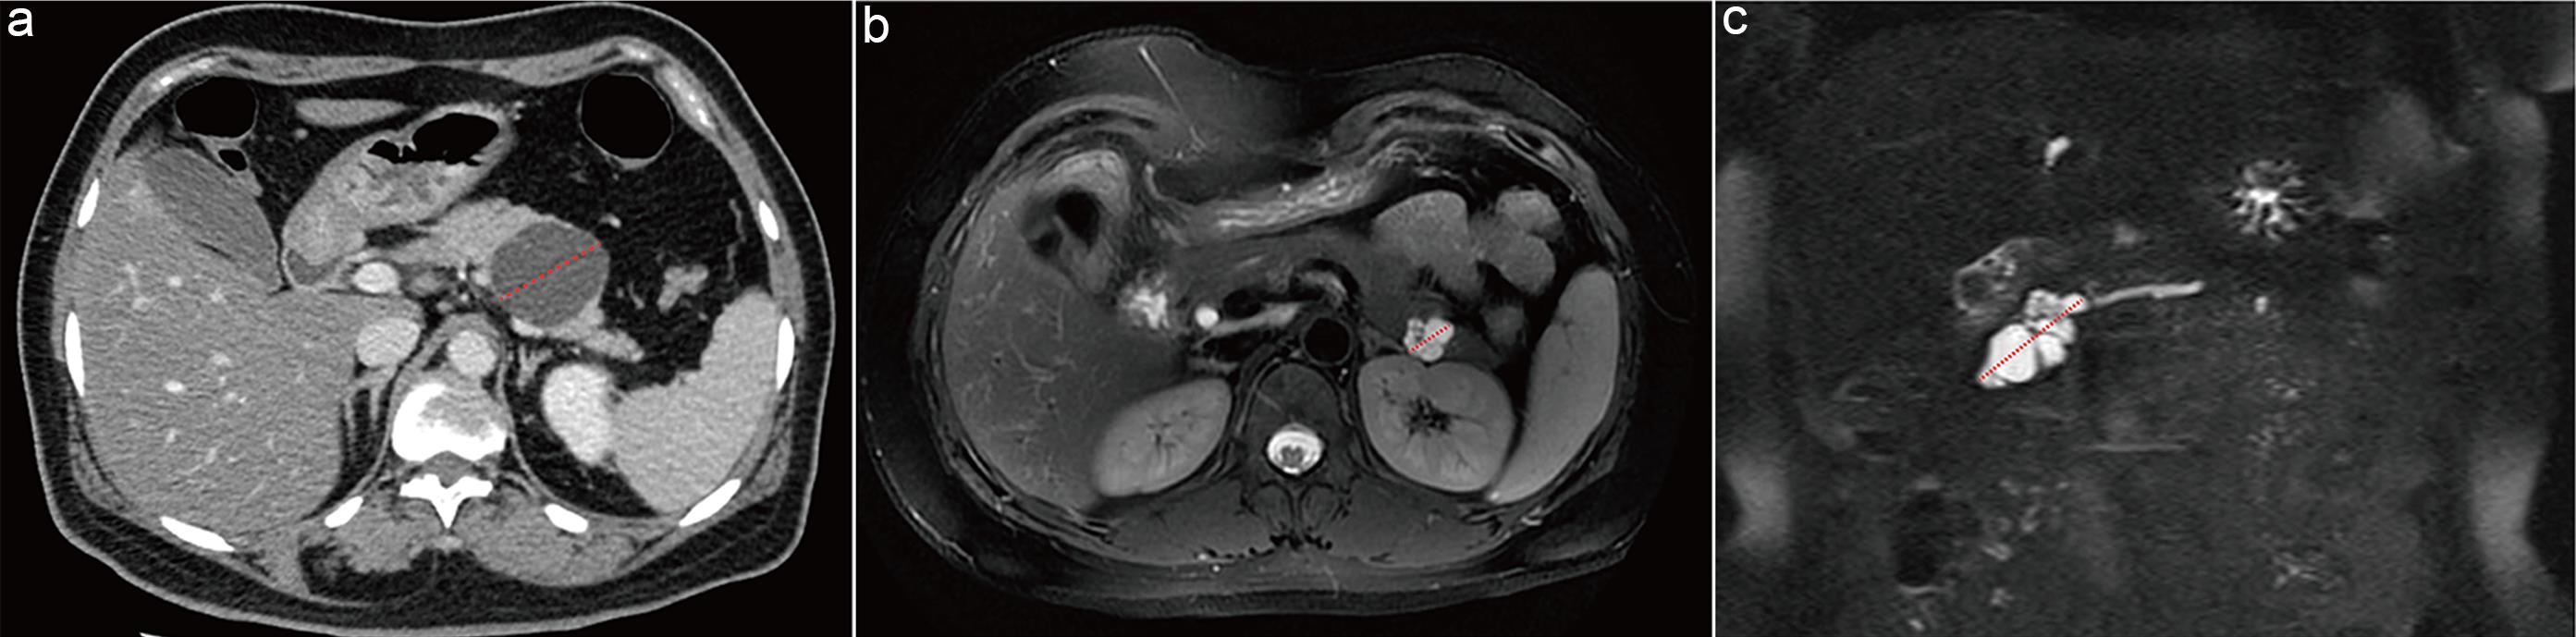

Recommendation 2: PCN size should be measured on contrast-enhanced CT during the pancreatic parenchymal phase and on MRI T2WI sequences.

On CT, the pancreatic parenchymal phase demonstrates homogeneous enhancement of normal pancreatic tissue, while PCN cystic fluid remains unenhanced, providing optimal contrast to delineate tumor margins (Fig. 2a).15 On MRI, T2WI is highly sensitive to cystic components, with PCN cyst fluid exhibiting high signal intensity against the background of normal pancreatic parenchyma, allowing clear tumor boundary visualization (Fig. 2b). Furthermore, Dunn et al.16 demonstrated that measuring PCN size on coronal T2WI improves interobserver agreement.17

Measurement methods for pancreatic cystic neoplasms.

Fig. 2  Measurement methods for pancreatic cystic neoplasms.

(a) Mucinous cystic neoplasm in the pancreatic tail. Axial contrast-enhanced pancreatic parenchymal phase computed tomography (CT) image demonstrating the optimal plane for measurement. (b) Serous cystic neoplasm in the pancreatic tail. Axial T2-weighted image demonstrating the optimal plane for measurement. (c) Branch-duct intraductal papillary mucinous neoplasm (BD-IPMN) in the pancreatic head. Coronal T2-weighted image demonstrating the optimal plane for measurement.